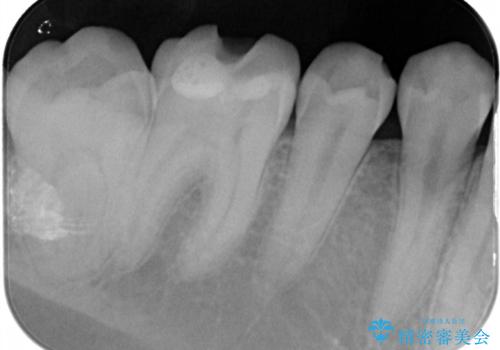

- 他院で行った、古いセラミックが欠けたとのことでご来院された患者様です。

古いセラミックを外すと、無数のヒビが入っており、そこからできた新しい虫歯がありました。

古い材料も虫歯もすべて除去して、根本からやりかえました。

セラミックが欠けるほど強い力がかかっているということは、ご自身の歯も割れている(小さいヒビ等も含む)可能性があります。拡大鏡でしっかり見ながら治療します。